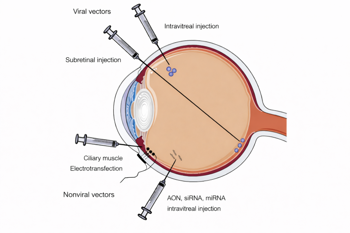

The integration of clinical and molecular data has paved the way for gene-targeted therapeutics, marking a paradigm shift in the management of IRDs. The development of such therapies depends on multiple disease- and gene-related factors. Disease-related considerations include the global burden of IRDs, degree of visual morbidity, age at presentation, disease stage and rate of progression. Gene-related factors include inheritance pattern, the functional impact of the mutation (eg. loss of function, dominant-negative effects) and practical considerations such as gene size, which influences vector-delivery strategies3 (Fig 1).

Fig 1. Routes of administration of viral and non-viral vectors in gene therapy3